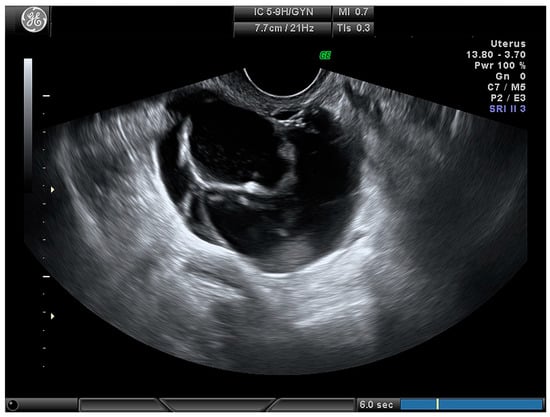

| Cystic–solid (Figure 4) | 61 (71.8) |